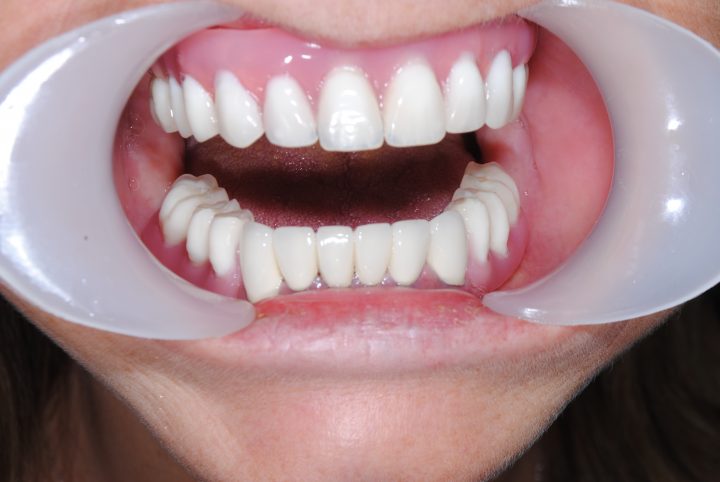

So, nach der 14 Wochen langen Heilungszeit, im Oktober 2017ist er zweites Mal nach Budapest geflogen, wann er oben und unten insgesamt 28 Stück metallfreie Zirkon Kronen im Ablauf 12 Tagen bekommen hat.

Peter macht noch immer Drachenflieger, aber trägt immer Zahnschienen zum Fliegen.